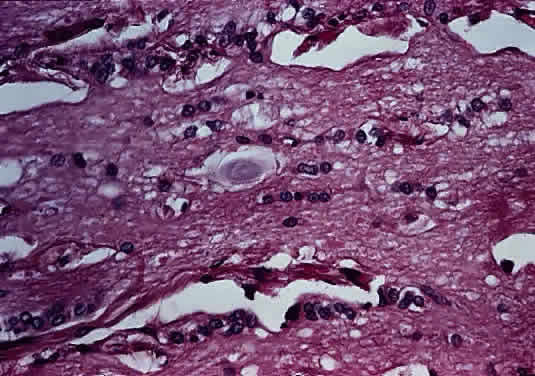

Intraoperatively, hemangioblastoma appears as a reddish, circumscribed tumor that typically is well demarcated from the nerve, although often the central portion is involved. Microscopically, the most striking feature is the abundance of vascular channels, most of which have the appearance of capillaries. Reticulin-staining highlights the vascular network. Between them are stromal cells containing abundant vacuolated cytoplasm, which is due to the presence of lipid. Although bland, the nuclei of the stromal cells are variable in appearance and may exhibit focal marked hyperchromasia (Figs. 46 and 47). Electron microscopy shows that the large stromal cells contain intracytoplasmic particles of lipid and glycogen. Scattered foci of extramedullary hematopoiesis may be present as a consequence of erythropoietin production by the tumor cells. Mast cells also are often readily identifiable. Small cysts are frequent, and the cyst wall consists of gliosis, in which may be found numerous Rosenthal fibers.

Fig. 46. Hemangioblastoma of optic nerve. Multiple capillary vessels are separated by foamy cells (hematoxylin and eosin staining).

Fig. 47. Hemangioblastoma of optic nerve. Foamy cells are a prominent feature between the thin-walled capillary vessels (hematoxylin and eosin staining).